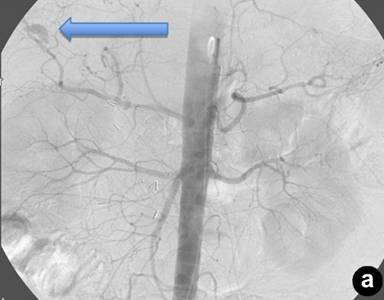

The patient returned three weeks later with near-syncopal symptoms, melena, and hematochezia. As the patient was exhibiting signs of intra-luminal bleeding, his first line diagnostic method was endoscopy which had to be repeated the following day due to clotted blood in the stomach. An additional 9 units of packed red blood cells were transfused. A tagged red-blood cell scan demonstrated bleeding localized to the proximal small bowel, and angiography demonstrated a right intra-hepatic artery pseudoaneurysm (Figure 2ab). The appearance of this pseudoaneurysm was small and intrahepatic and there was no extravasation of contrast or communication with the biliary tree. However, this was the likely source of bleeding and therefore we proceed to embolize it expeditiously. The patient had two straight 2 mm microcoils and two vortex microcoils of 3 ad 3.3 mm placed for selective embolization. After the procedure, the patient’s hematocrit stabilized, and he had no further episodes of hypotension or gastrointestinal bleeding. He is currently doing well without any sequelae nine months after surgery.

Figure 2. Right intra-hepatic artery pseudoaneurysm. Note the proximity of the percutaneous transhepatic cholangiography catheter (a.) to the location of the pseudoaneurysm (b.). |